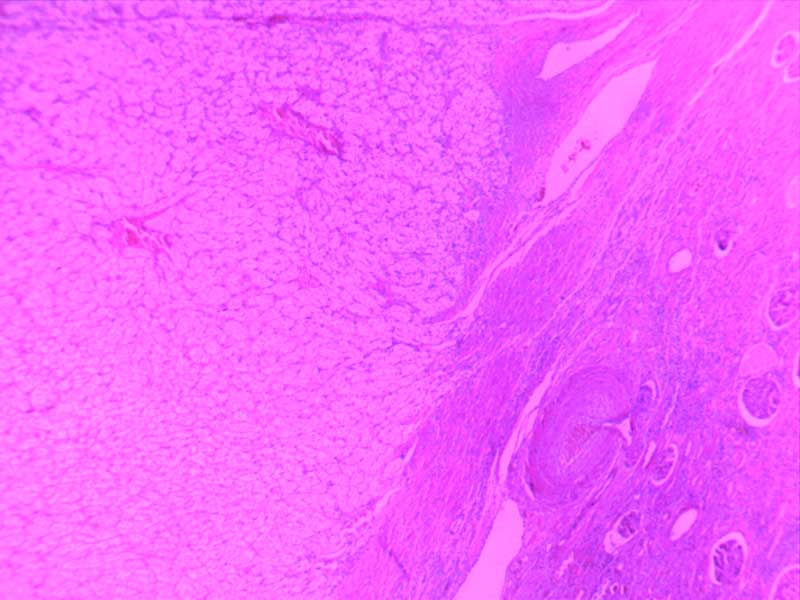

主动脉粥样硬化-10倍